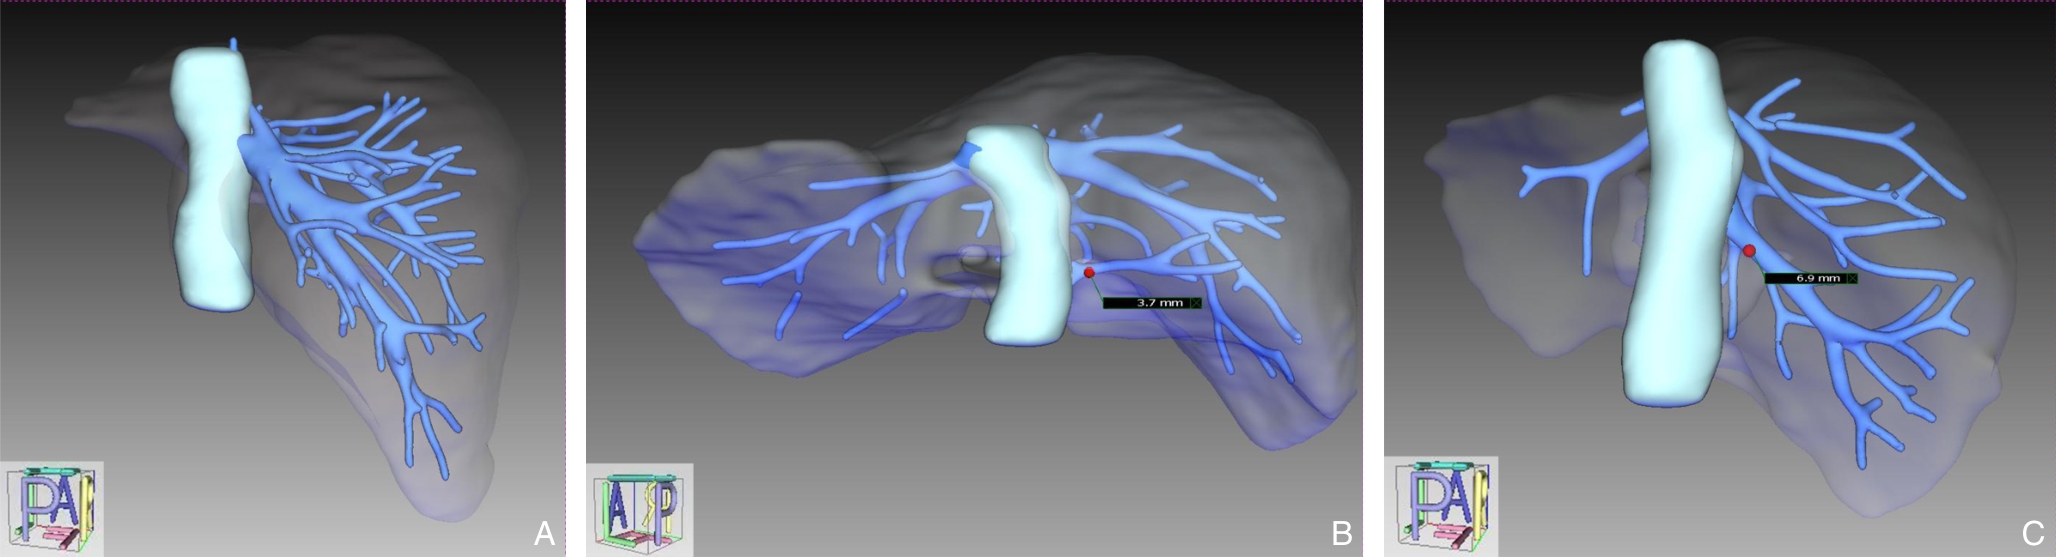

- 混合现实辅助胸骨后甲状腺肿手术的可行性与安全性分析:附29例报告